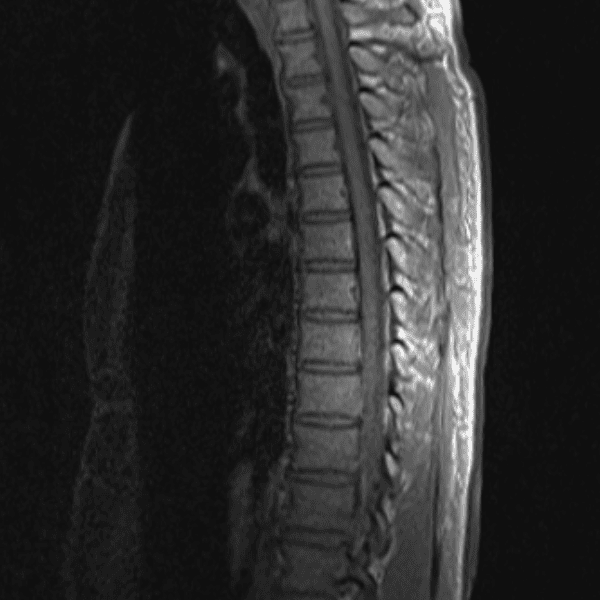

Simulates call by including subtle or difficult cases and some normals.

35 cases